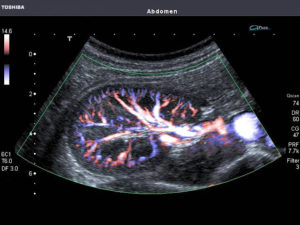

Суть процедуры ЦДК

Цветовое доплеровское картирование – это метод, который дает возможность оценить кровоток в сосудах. Основа исследования – это комбинация двухмерного изображения и оценка кровотока в соответствие с доплерометричными показателями.

Диагност выводит на экран изображение привычное для ультразвука, а в месте, которое изучается, в цвете представлены кровяные потоки и соответственно их скорости. На мониторе будет видно следующие цвета:

- Красные потоки – это кровь, которая движется к датчику.

- Синие потоки – кровь, которая следует от датчика.

О скорости можно судить по интенсивности цвета, чем он менее выражен, тем медленней движется поток. Метод ЦДК не только отображает визуальную картинку, но и анализирует направленность, стремительность, характер кровяного потока. Также исследуется проходимость сосудов почки, их диаметр, сопротивляемость.

- Цветная доплеровская диагностика помогает врачу получить информацию о состоянии сосудов и интенсивности движения крови, ошибки почти исключаются. На мониторе отображается кровоток к датчику с помощью красного цвета, а от датчика – голубого. Яркость соответствует скорости кровообращения.

Доплерография дает возможность оценить степень проходимости сосудистого русла по полученным графикам тока крови. Иногда при доплеровском исследовании врач использует способ ЦДК (цветовое доплеровское картирование), фиксирующий скорость кровотока.

Затем, используя режим допплерографии, изучают кровоток. Специальная компьютерная программа обрабатывает информацию, полученную от датчика, и выводит ее на экран в виде цветной картинки и графиков. Чем выше скорость крови, тем ярче изображение. Поэтому можно не только судить о скорости кровотока, но и определить препятствия току крови, их местоположение, размеры.

В режиме ЦДК определяют скорость кровотока, наличие завихрений, которые указывают на повреждение интимы, наличие атеросклеротических бляшек, тромбов. В таких случаях при картировании выявляется сужение просвета сосуда. Участок повышенного кровотока может указывать на злокачественное новообразование.